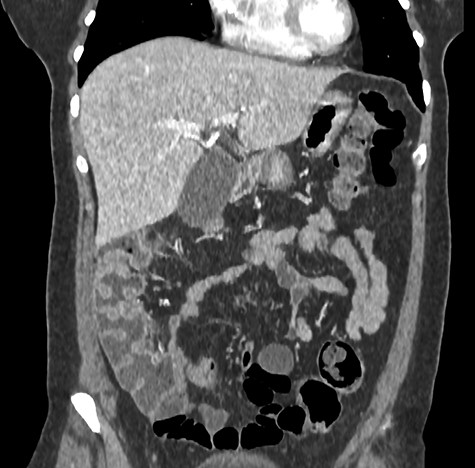

A 44-year-old female patient, without prior abdominal surgery, was admitted to the emergency department with an acute epigastric abdominal pain, without nausea. She presented similar episodes of pain in the past, without having ever requested a medical opinion. Physical examination revealed an acute epigastric pain without signs of peritonitis. Laboratory analyses were within normal limits. A computed tomography showed an internal hernia of the colon in the lesser sac, going back from the liver pedicle (Fig. 1). There were neither occlusion nor ischemia. We performed immediately a diagnostic laparoscopy with one 11-mm umbilical port and two 5-mm ports (one in the left lumbar and one in the hypogastrium). Exploration confirmed that the ascending colon and the right colonic flexure had herniated through the foramen of Winslow (Fig. 2). The colon was reduced with an atraumatic Johann’s graspers and was viable, cecum, ascending colon and the right colonic flexure was mobile due to a misapposition of the right Told fascia. To prevent recurrent herniation we performed the fixation to the lateral wall of the cecum, ascending colon and right colonic flexure with several non-absorbable sutures (Fig. 3). We did not perform the closure of the Winslow’s hiatus. Postoperatively, the patient recovery was uneventful and was discharged home 2 days later. A computed tomography was performed 1 month later for another reason, showing a good result of the right colon fixation on the lateral wall (Fig. 4). Twenty months after surgery, the patient totally recovered and has not experienced any recurrence or occlusion.

Computed tomography showed an internal hernia of the colon in the lesser sac, going back from the liver pedicle.